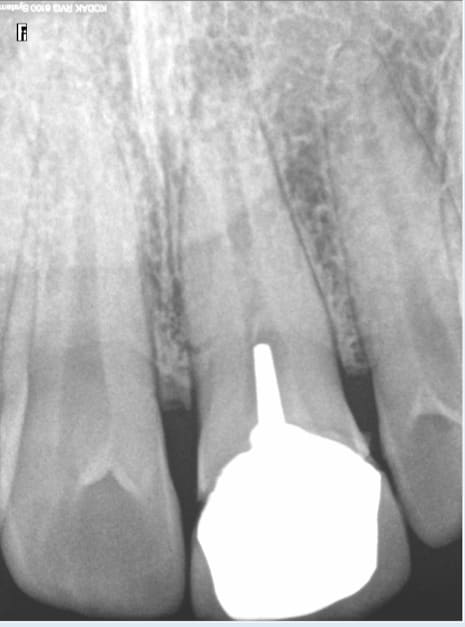

Et c'est loin d'etre un cas isolé, celui là commence à ressentir une légère gène sur cette 14 traitée depuis des années. -)

Des exemples comme ca il y en a à l'infini. Ils devraient imposer des tarifs gratuits pour les endos, ca augmenterait encore plus la qualité. -)

chicot29 écrivait:

------------------

> Et c'est loin d'etre un cas isolé, celui là commence à ressentir une légère gène

> sur cette 14 traitée depuis des années. -)

> Des exemples comme ca il y en a à l'infini. Ils devraient imposer des tarifs

> gratuits pour les endos, ca augmenterait encore plus la qualité. -)

Du coup je me demande comment la personne qui a fait ça peut dormir sur ses deux oreilles en regardant la radio de contrôle. Mais il y en a sûrement pas eu, il devait être sûr de son coup. Je comprends pourquoi cette personne choisit des tenons plutôt cours en tout cas.